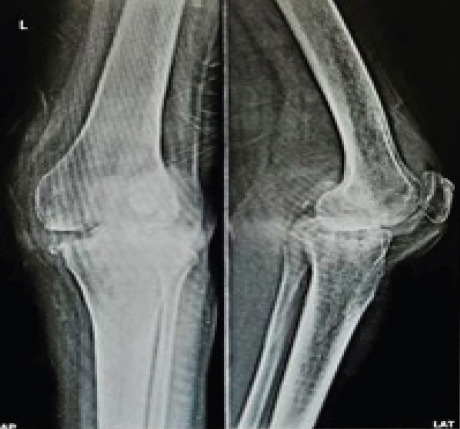

Case report: A 55-year-old female patient of South Asian descent presented with progressive left knee pain and restricted range of motion. Clinical and radiological investigations revealed signs of inflammatory pathology, including elevated serum markers and imaging findings consistent with arthritis. Histopathological examination of the synovial tissue confirmed tubercular arthritis. The patient underwent surgical debridement followed by TKA. Postoperatively, the patient demonstrated significant functional improvement and was closely monitored over a 2-year follow-up period, with no recurrence of infection or prosthesis-related complications.